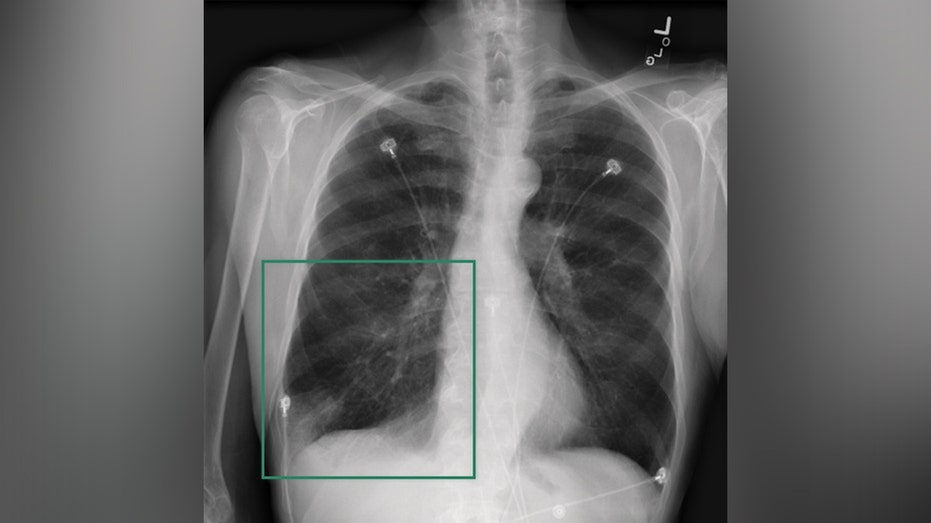

صورة الملف: تم تصوير الأشعة السينية هنا. يمكن لـ Aidoc تحليل صور الأشعة للمساعدة في اكتشاف السكتات الدماغية والحالات الحرجة الأخرى. (نفيديا)

وفي الوقت نفسه، يستطيع Aidoc تحليل صور الأشعة للمساعدة في اكتشاف السكتات الدماغية وغيرها من الحالات الحرجة بسرعة أكبر.

وقال باول: “كل ثانية من السكتة الدماغية تسبب في الواقع المزيد والمزيد من تلف الدماغ”. “وهكذا لديهم هذه العناصر البصرية الأساسية التي تعمل في الخلفية، وتكون قادرة على النظر إلى كل صورة من خلال النظام والبحث عن أشياء حادة كهذه، حتى نتمكن من فرز المرضى بشكل أسرع.”

وقال باول: “يمكنك أن تطرح عليه سؤالاً مثل: هل يمكنك أن تخبرني إذا كان هناك أي تشوهات في هذه الأشعة السينية؟”. “وسوف يمر عبر سلسلة الأفكار الدقيقة التي تعلمها أخصائي الأشعة في مدرسته، وسوف يقرأها لك.”